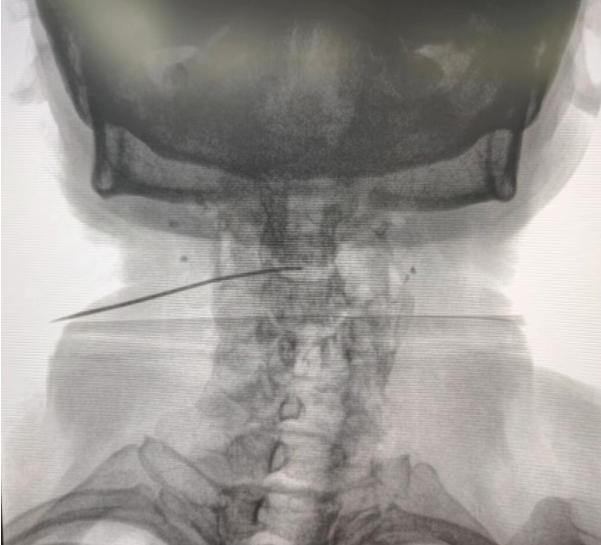

颈椎间盘射频消融联合胶原酶化学溶解术后